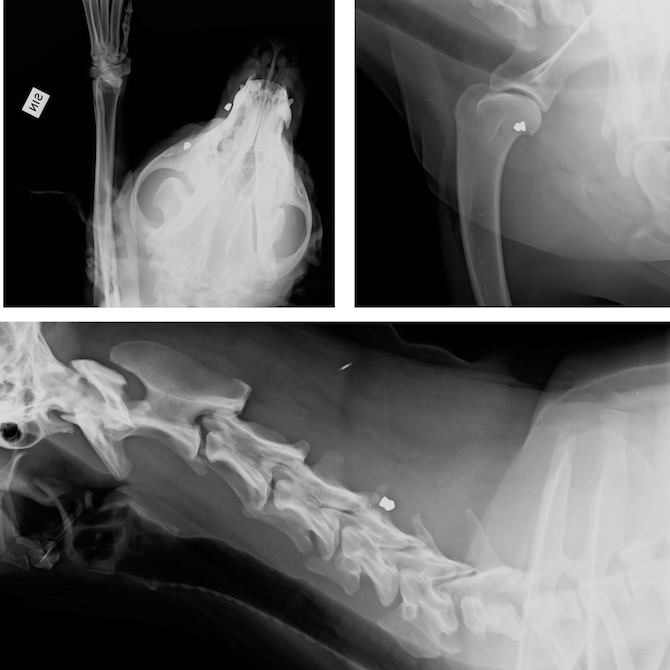

Epulta löytyi ilmakiväärin ammuksia eri puolilta kehoa. Niiden sijainnin vuoksi ne päätettiin poistaa, sillä niiden epäiltiin aiheittavan sille kipua ja hermoärsytystä.

Eppu jää kummikoirana yhdistyksen omistukseen ja saa asua tutussa hoitoperheessään. Viipurin Koirien vastuulla on etsiä Epulle rahat sen jatkuviin lääkityksiin. Yhdistys on tukenut Eppua tähänkin saakka ja sille on järjestetty myös erilliskeräyksiä mm. kiputukimusta, röntgentutkimusta, luotien poistoa ja hammaslääkäriä varten. Eppu käy toisinaan myös hierojalla.